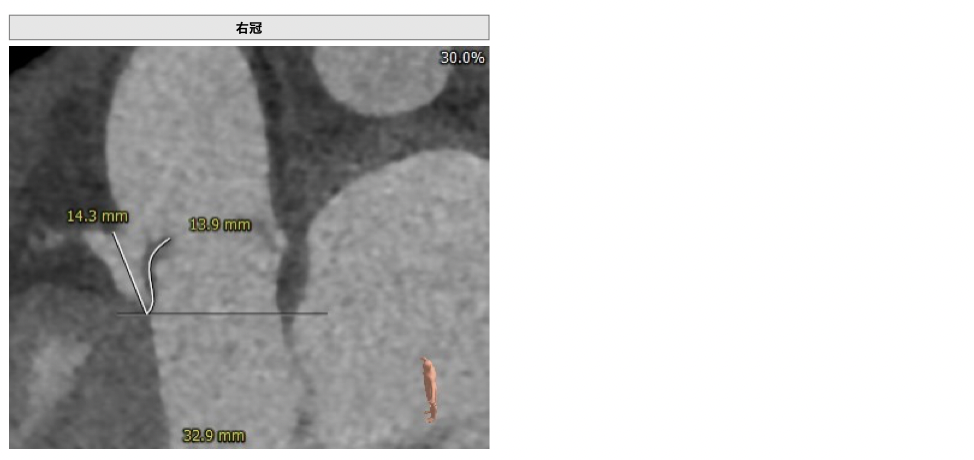

CT检查

①患者因规律透析导致钙磷代谢紊乱,外周血管斑块钙化严重,最狭窄处仅2.8mm,通路建立难度极大(左右颈动脉均不符合入路条件);